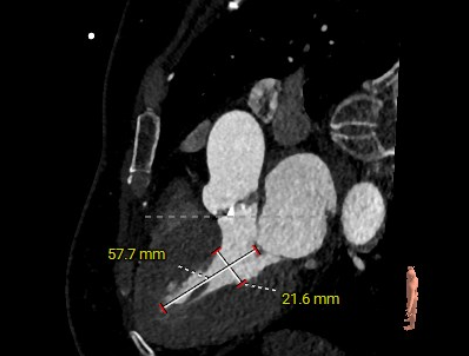

主动脉根部评估:

短轴

长轴

三叶式主动脉瓣,瓣环周长69.1mm,平均周长径22mm,LVOT周长径22.5mm,STJ周长径23.6mm,SOV瓦式窦:平均周长径 26.9mm,升主动脉最大直径30.2mm。

左冠高度9.7mm 右冠高度14.0mm,左冠冠脉开口高度小于瓣叶长度,右冠脉开口高度大于瓣叶长度,综合考虑可能存在左冠阻挡风险,术中球囊预扩须密切注意冠脉灌注。

瓣叶轻度钙化伴增厚,钙化分布不均匀

HU1460 积分70mm²

左室腔内径正常,心室壁增厚